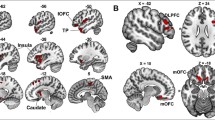

The purpose of the current study was to investigate the relationships between CR, FBL, and cognitive performance in a sample of healthy adults over age 50. Specifically, we examined whether CR moderated the relationship between FBL and cognitive performance. We hypothesized individuals with higher CR would demonstrate better cognitive performance despite similar whole brain FBL, compared to individuals with lower CR. As a secondary aim, we evaluated the relationships between CR, cognitive performance, and FBL in specific white matter association tracts including the cingulate gyrus segment of the cingulum (CGC), hippocampal segment of the cingulum (CGH), inferior fronto-occipital fasiculus (IFOF), and uncinate fasiculus (UF). Premorbid IQ (using the Wide Range Achievement Test-4- reading subtest; WRAT-4) was used as our measure of CR.

FA images were registered with the Johns Hopkins University (JHU) white matter atlas using affine registration and FSL FLIRT to examine anatomical features of specific tracts. Tracts including the CGC, CGH, IFOF, and UF were selected due to previously established associations with global cognition (Baek et al. 2013; Booth et al. 2013; Cremers et al. 2016). Each tract was modeled separately by hemisphere and streamlines were selected for inclusion in each bundle using the JHU atlas regions-of-interest. Fibers were included in the bundle if at least 80 % of the arc length was contained in the bundle mask, and streamlines were culled within 0.8 mm of an existing tract were used to reduce redundancy (Zhang et al. 2003). FBL was computed from the total length of the streamlines included in the bundle. Eight participants failed processing during tract-specific analysis and therefore were only included in the whole brain analysis. FBL was normalized by dividing by total intracranial volume (Correia et al. 2008).

The main effects regression model of total RBANS score onto the CGH and CR demonstrated that FBL in the CGH predicted RBANS performance at a trend level F(2,52) = 2.64; p = 0.08, R2 = 0.09, f2 = 0.09, accounting for 9 % of the variance in RBANS performance. Results indicated that higher CR was associated with better RBANS performance at a trend level (t = 1.77, p = 0.08). However, longer FBL was not significantly associated with better RBANS performance in the CGH (t = 1.00, p = 0.32). The regression with an interaction included (CGH FBL*CR) was significant (F(3,51) = 3.13 p = 0.03, R2 = 0.16, f2 = 0.19), accounting for 16 % of the variance in RBANS performance. The higher adjusted R2 in the interaction model demonstrated that the regression that included the interaction term was a better fit of the data and this was confirmed by an ANOVA (F(1,51) = 3.82, p = 0.06, Cohen’s d = 0.53). There were no significant main effects or interactions observed in the CGC, IFOF, UF regression models (p’s > 0.05).